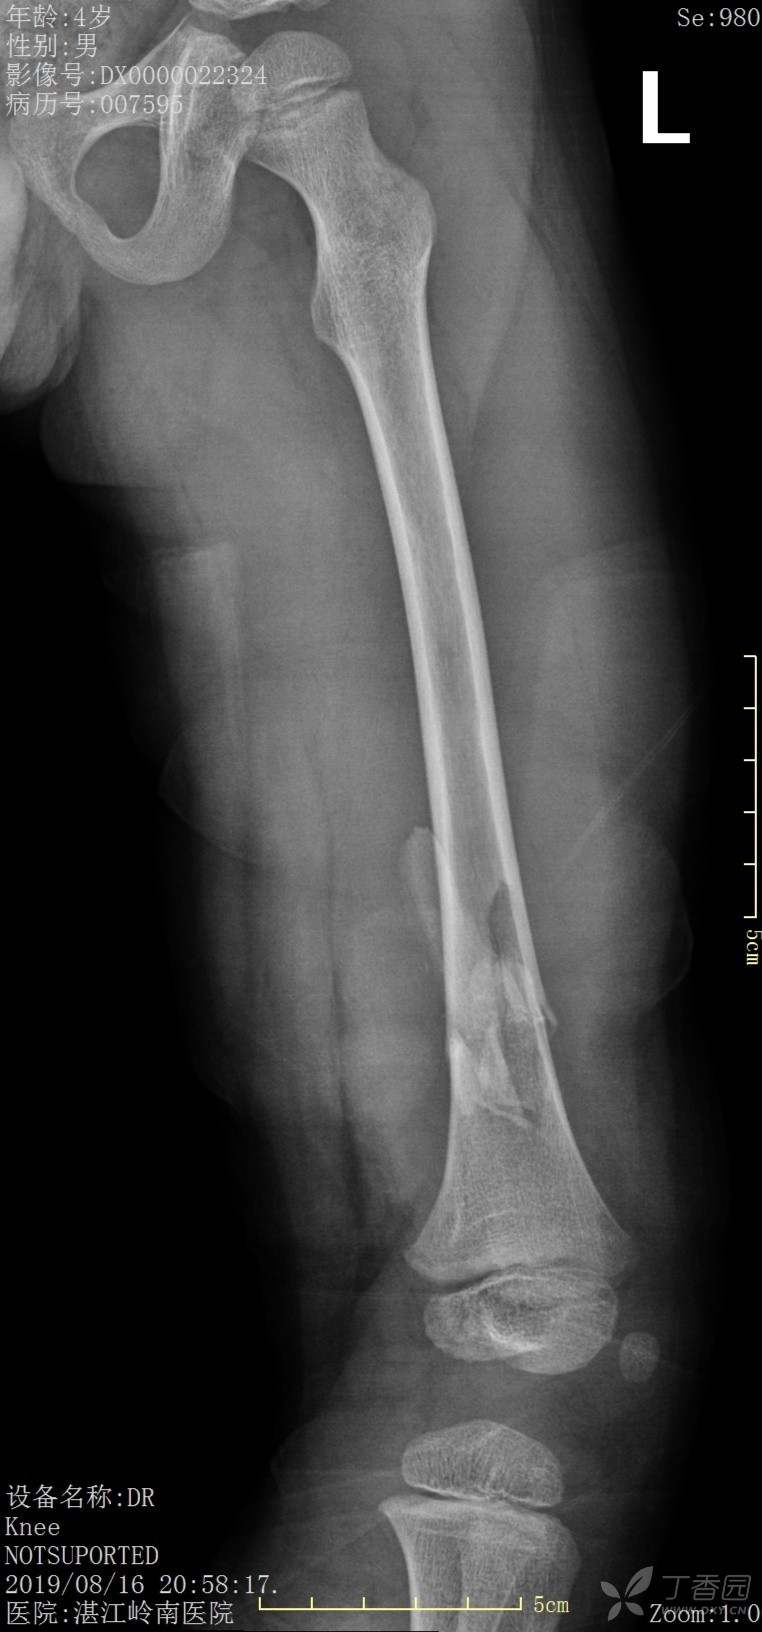

4岁患儿股骨骨折保守治疗一例

外伤时,保守1个月、2个月、6个月